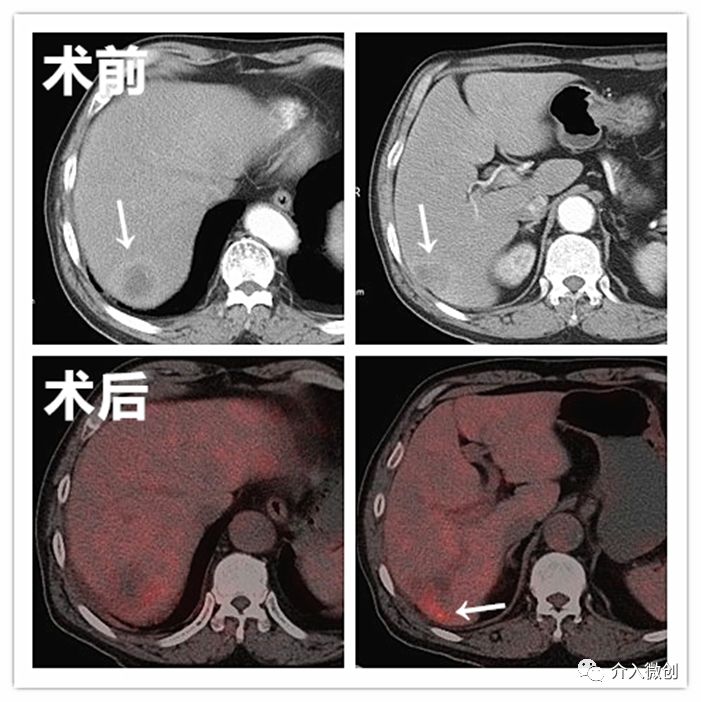

病例2

老年女性患者,诊断为乙状结肠腺癌并肝多发转移。肝脏肿瘤病灶巨大且多发,针对肝脏转移瘤行载药微球栓塞治疗,肠道肿瘤行动脉化疗灌注治疗。

肝动脉化疗栓塞+肠系膜上动脉化疗灌注治疗

术后1月复查提示肝转移瘤病灶内部明显坏死,肿瘤缩小